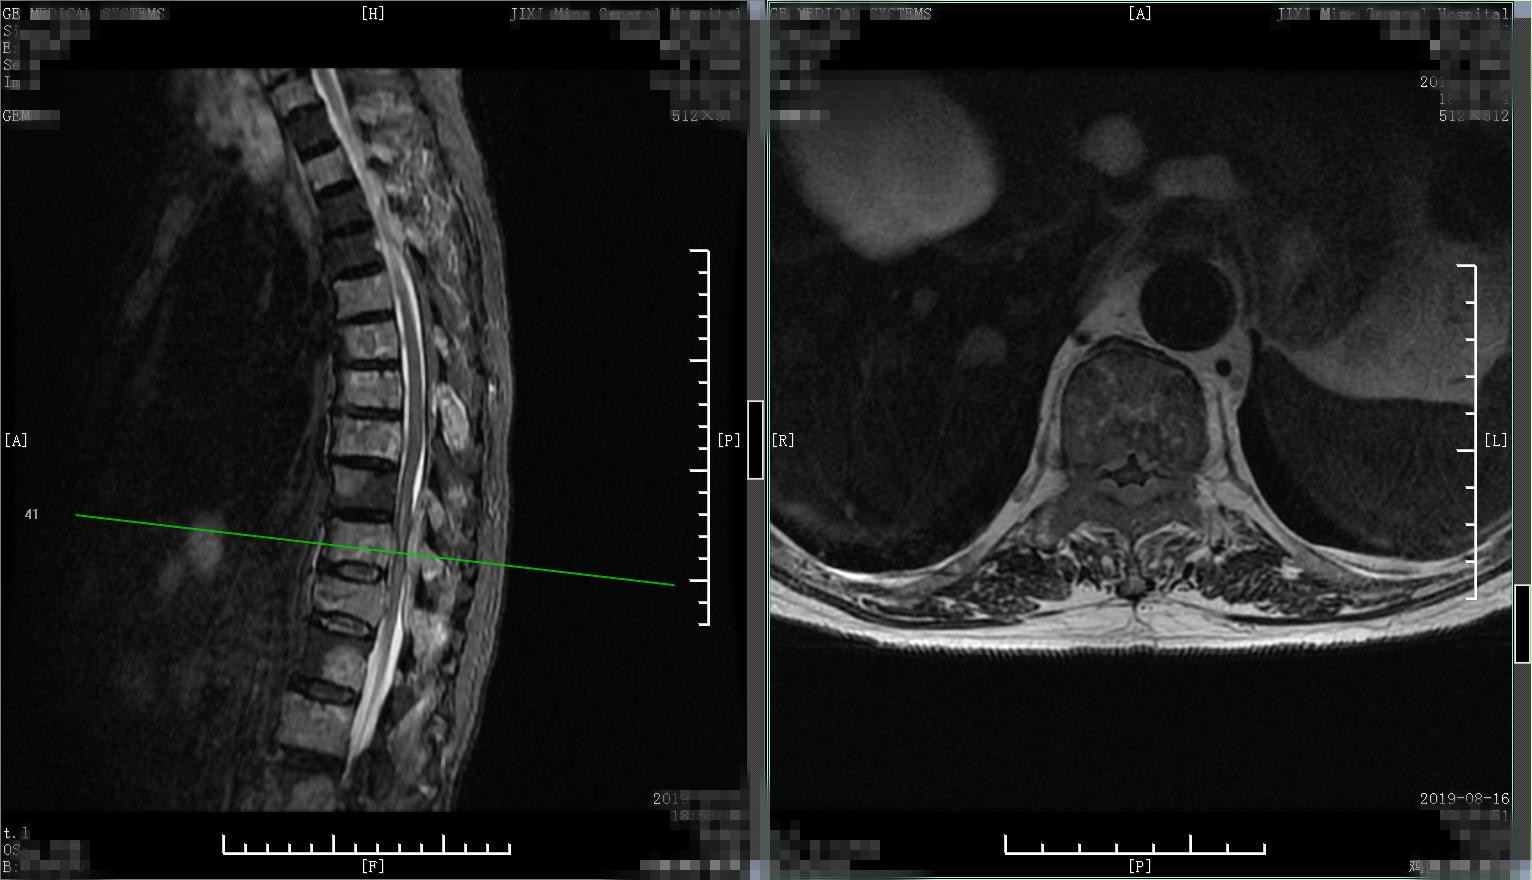

患者1、男性、57岁,病人就诊前2个月逐渐出现腰背部疼痛进行性加重,无外伤史,自行外贴膏药、口服活血化瘀药物、热敷治疗,起初症状略减轻,但1个月后逐渐出现疼痛加剧,变换体位及活动均明显收到影响,夜间常自感低热,半夜常被疼醒。查腰椎X线片,发现腰1、胸12椎体轻度变扁,骨质疏松,疼痛是什么原因,难道是骨质疏松导致的椎体压缩性骨折?所以进一步又查胸腰椎核磁,结果如下,椎体弥漫性异常信号改变,胸12、腰1椎体病理性骨折。

椎体多发异常信号

椎体多发异常信号,胸12、腰1椎体骨折

最终结合骨髓穿刺及血液生化检查,确诊为 多发骨髓瘤 ,骨髓瘤发病以40-60岁人群居多,胸椎及腰椎好发,四肢长骨较少受到侵犯,主要表现为进行性加重的胸背部疼痛,同时常伴于贫血、乏力、消瘦、感染等表现,当出现病理性骨折时可导致疼痛加剧,严重时可压迫脊髓产生症状。此病人转入血液科规范化疗,腰背部疼痛逐渐改善。